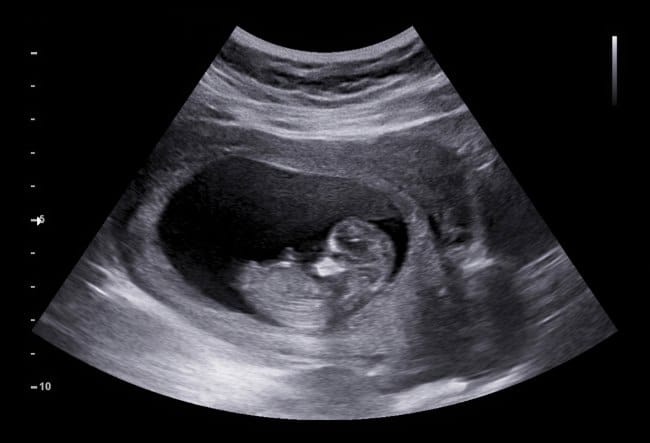

Berikut ini adalah beberapa ciri utama bentuk janin 3 bulan yang bisa diamati melalui USG atau berdasarkan proses pertumbuhan alami di dalam kandungan:

- Ukuran janin sekitar 5–7 cm, seberat buah anggur besar atau lemon kecil

- Kepala janin masih tampak lebih besar dibanding tubuhnya, karena otak tumbuh sangat cepat

- Wajah mulai terbentuk, dengan posisi mata sudah berpindah ke bagian depan kepala dan kelopak mata mulai menutup

- Telinga luar, hidung, dan bibir makin jelas bentuknya

- Tangan dan kaki sudah tumbuh lengkap, termasuk jari-jarinya yang bisa digerakkan meski masih kecil